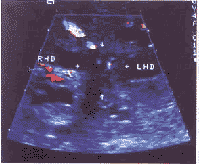

本组病例肿瘤内血流显示率为 64.3%,以点状、短线状彩色血流多见(图2,3)。文献报道[1]肝门部胆管癌多属于硬化型少血供的肿瘤,本组肿瘤血流显示率较高,可能与选择的病例有关。1/3的病例合并胆囊癌,在病理学上胆囊癌分化程度低,生长迅速,肿瘤内血供较丰富。

图2 肝瘤内点状彩色血流

图3 肿瘤内短线状彩色血流,脉冲多普勒测及动脉频谱